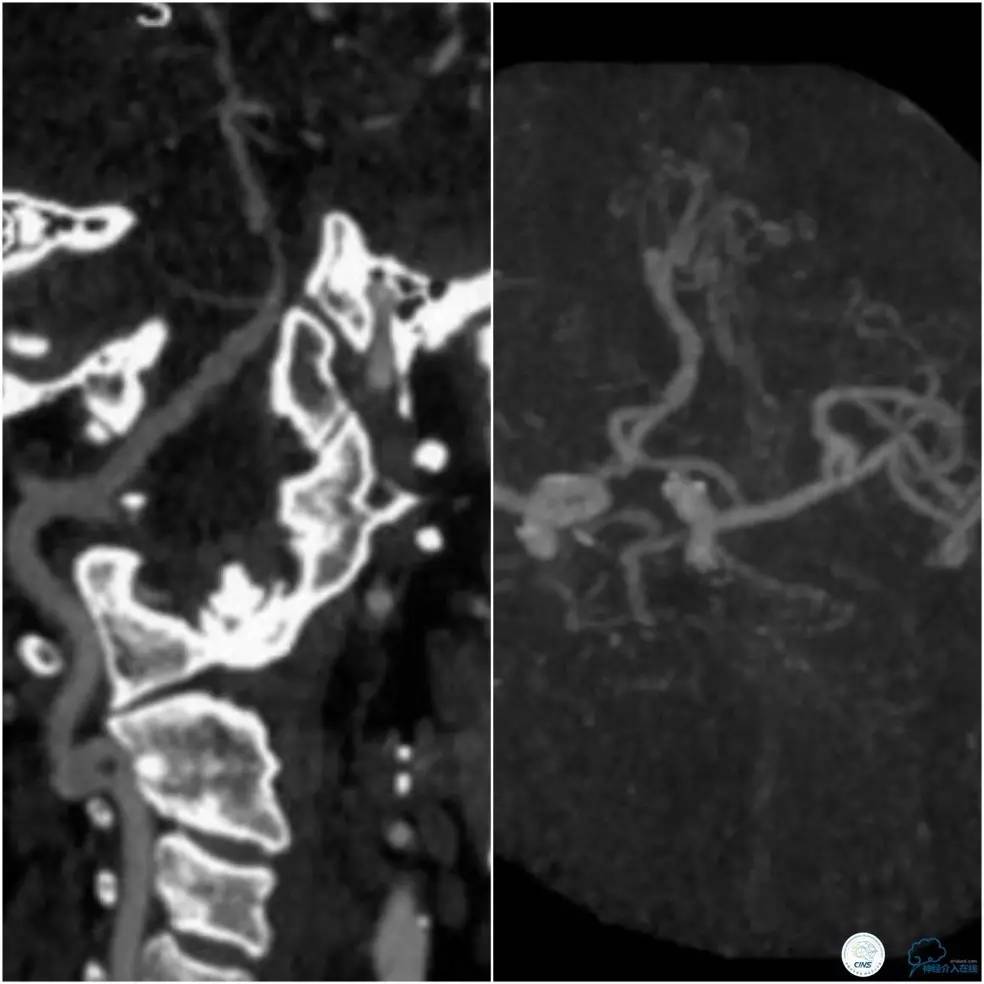

头颈部CTA示基底动脉及右侧椎动脉V4段狭窄,基底动脉狭窄远端局部管腔扩张(图2)。

图2